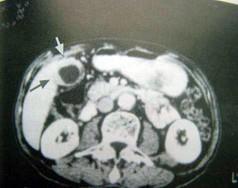

问题 女,58岁,上腹部疼痛半月,无畏寒、发热、黄疸等症状,CT检查如图,最可能的诊断是 ( )

选项 A.慢性胆囊炎 B.胆囊癌(胆囊壁增厚型) C.胆囊腺肌增生症 D.胆囊息肉 E.胆囊转移瘤

答案 B